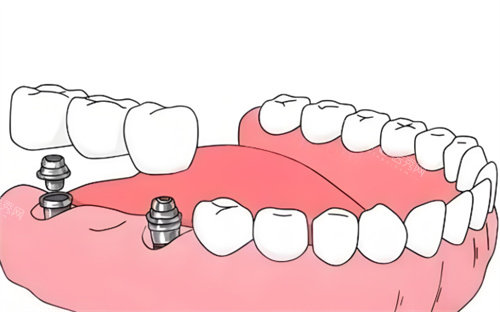

伊诺种植体系统包含种植体、基台和牙冠三部分。种植体植入牙槽骨内作为人工牙根,基台连接种植体和牙冠,牙冠则是可见的牙齿部分。该系统提供多种规格,可以适应不同患者的牙槽骨条件。